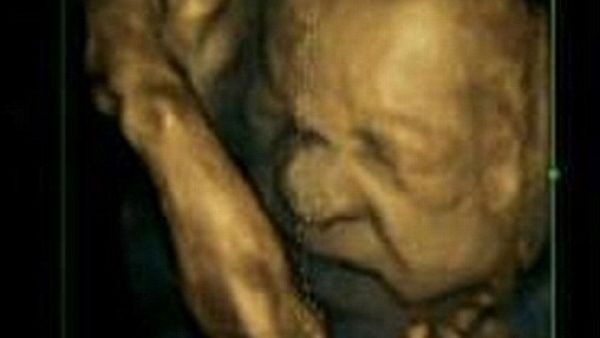

عل رأيت تعابير وجه جنين قبلاً..